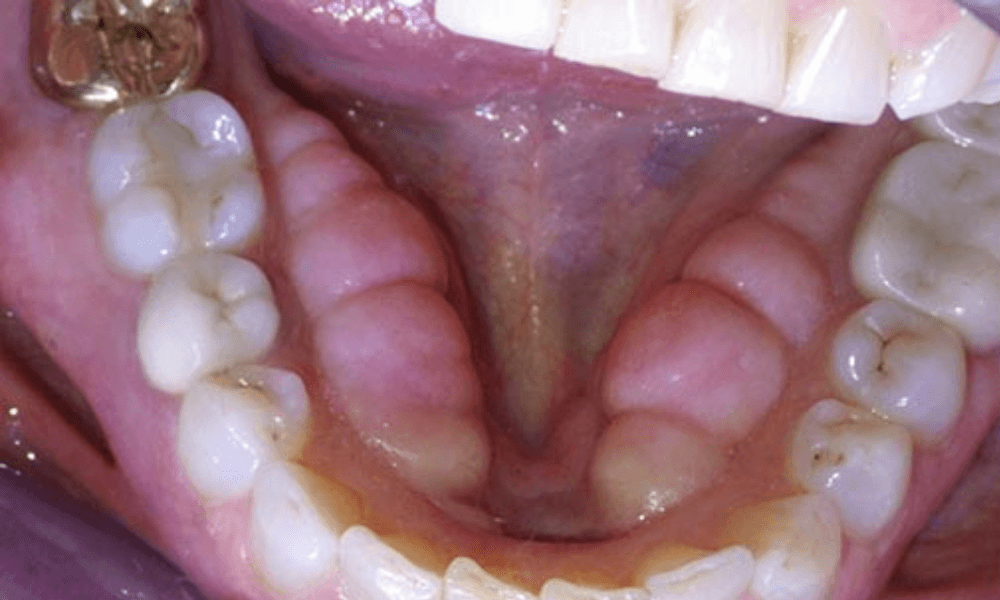

Mandibular Tori Pictures

Mandibular tori are bony growths that appear on the inner surface of the lower jaw. These growths are typically harmless and vary in size and shape. In the pictures provided below, you can observe the different presentations of mandibular tori. These images will help you recognize what mandibular tori look like and understand their typical appearance. If you notice similar growths in your mouth, it’s advisable to consult a dentist for a professional evaluation.